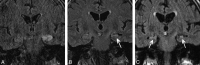

Results: Thirty-three of 42 patients (78.6%) demonstrated enlargement and T2 hyperintensity of mesial temporal lobe structures at some time point. Mesial temporal sclerosis was commonly identified (16/33, 48.5%) at follow-up imaging. Six of 9 patients (66.7%, P = .11) initially demonstrating hippocampal enhancement and 8/13 (61.5%, P = .013) showing hippocampal restricted diffusion progressed to mesial temporal sclerosis. Conversely, in 6 of 33 patients, abnormal imaging findings resolved.

Conclusions: Autoimmune voltage-gated potassium channel complex encephalitis is frequently manifested as enlargement, T2 hyperintensity, enhancement, and restricted diffusion of the mesial temporal lobe structures in the acute phase. Recognition of these typical imaging findings may help prompt serologic diagnosis, preventing unnecessary invasive procedures and facilitating early institution of immunotherapy. Serial MR imaging may demonstrate resolution or progression of radiologic changes, including development of changes involving the contralateral side and frequent development of mesial temporal sclerosis.